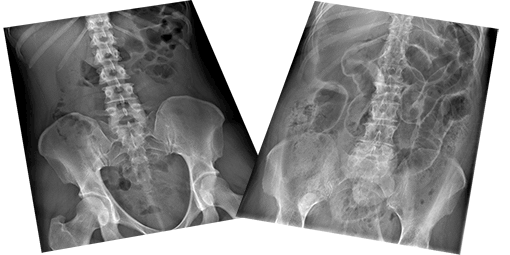

Abdominal X-ray X-ray Interpretation - Course Completion Assessment

- Abdominal X-ray - System and anatomy

- Abdominal X-ray - Abnormal bowel gas pattern

- Abdominal X-ray - Abnormal calcification

- Abdominal X-ray - Abnormal soft tissues and bones